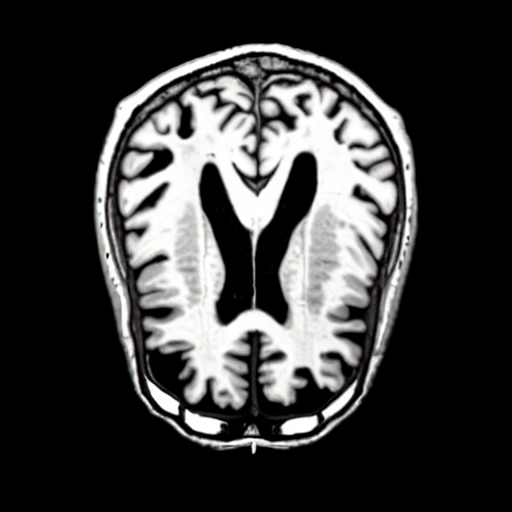

We present the results of conditional medical image generation with and without our proposed method LD, in Tab. 1, and Fig. 5. In Fig. 4, we show examples of brain MR images generated by the different methods combined with LD for two different classes of cognitively normal (CN) and Alzheimer’s disease (AD). The results were obtained by fine-tuning the corresponding method on the medical data with LD. As shown in Fig. 4, the samples generated through Custom Diffusion tuning are realistically looking while understanding the difference between CN and AD brain properly, which other methods failed at. Textual inversion seems to understand the concept but fails to understand the brain structure properly. Quantitative results on the performance of all our methods are presented in Tab. 1. Qualitative results on the CheXpert [19] dataset, along with a user study and ablation of different parameters, optimization algorithm, and more, are included in the supplementary material.

Qualitatively, Fig. 5 shows a significant improvement of the visual realism across all methods when using a drift of . The background is consistently black as in real brain MR images; the shape of the brain becomes more realistic, and the white and gray matter structure improves. For an analytical evaluation, we calculated the FID between our test data and 200 synthetically generated images from each method (100 CN, 100 AD). The results in Tab. 1 demonstrate that LD improves the ability of the model to generate realistic MRI slices for both healthy brains and brains with Alzheimer’s disease. For this reason, all following experiments were done with LD.

We use the Pix2Pix Zero model with a basic fine-tuned Stable Diffusion model to generate healthy brain MRIs from ones diagnosed with Alzheimer’s Disease and vice versa. We generate the counterfactual images by negating the ground truth label of the 200 test samples and conditioning the model on the negated label value and the source image. We compute image quality metrics, as well as the AUC, using a disease classification model trained on 600 real brain MRI slices (300 AD, 300 CN). Additionally, we determine the Structure Similarity Inced (SSIM) between the target and the source image to determine how well the identity of the source image is retained. The qualitative results in Fig. 6 , illustrate four examples from our two editing directions: from AD to CN and from CN to AD, respectively. When transitioning from AD to CN, the model primarily reduces the size of the ventricles. Conversely, in the CN to AD transformation, the ventricle size increases, accompanied by a worsening of brain atrophy.